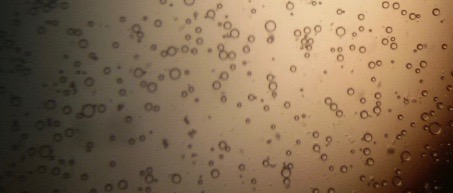

Proniosomes were transformed to noisome by hydrating with 10 ml distilled water at 37 °C and gentle agitation using vortex mixer (MaxiMix II, USA) for 5 min. The formed niosomes were sonicated twice for 30 seconds using sonicator (SONICS VCX 130, USA) [25]. The niosomal dispersion was put on a glass slide, and the formed vesicles were observed at a magnification of 1000x through an optical microscope. The formation of vesicles was observed using an optical microscope and photomicrographs were recorded [26].

The optical photographs of all reconstituted proniosomal formulae are shown in fig. (1-28). The photographs revealed that the formed niosomes are unilamellar vesicles with a spherical shape and smooth surface. The vesicles were insular and separate without aggregation or lumping. Apparently, proniosomal formulae containing span 40 and span 60 yielded vesicles of large numbers with well-identified outline and core which will affect the entrapment efficiency of loaded drug directly. However proniosomal formulae containing span 20 and span 80 produced small numbers of vesicles with a slightly different outline. This may be due to the high phase transition temperatures of both span 40 and span 60 which will cause the formation of a large number of stable niosomal vesicles. The phase transition temperatures for span 20, 40 and 60 are 16, 42 and 53 °C; respectively, however, span 80 possess the lowest phase transition temperature at 12 °C [35]. This explains why proniosomal formulae containing span 20 and span 80 produce small numbers of vesicles upon hydration.